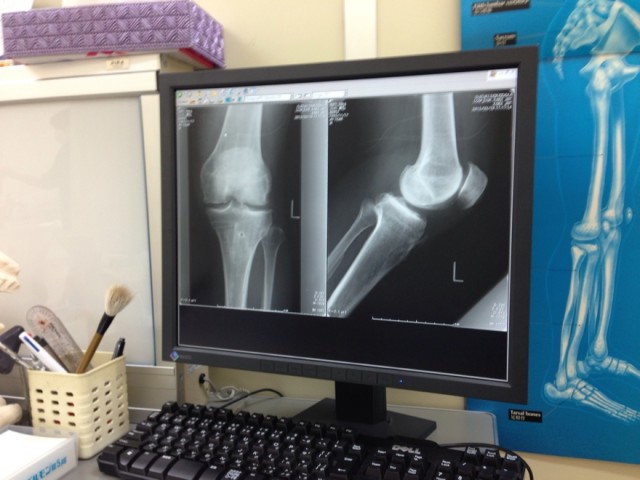

レントゲンを撮ると、30年間、空手やキックボクシングで酷使してきた膝は、ボロボロになっていました。

診断は、膝十字靱帯損傷、膝内側靱帯断裂。

だけど、もう手術をすることもできないほど、軟骨がすり減っていて、あとは筋肉でカバーするしかないと言われました。